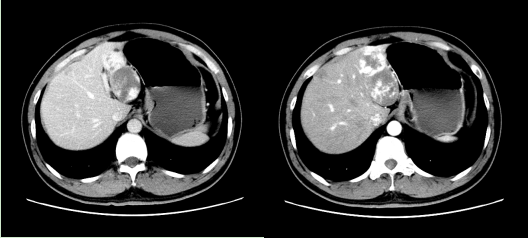

患者,男性,43岁,居住于呼伦贝尔,因“发现肝左侧占位3年,且逐年增大”就诊我院,既往有膝关节半月板损伤病史,上腹部增强CT如下图示。

入院后完善相关检查,多学科会诊,考虑患者肝占位为血管瘤可能性大,按照《肝血管瘤诊断和治疗多学科专家共识》,患者具备干预指征,同时患者合并半月板损伤,决定对患者进行联合手术治疗。2021年8月3日在手术麻醉科白艳艳主任、器械护士李瑞小护师、巡回护士娜娜护士长密切配合下,肝胆外科张俊晶、薛超、王勇组成腔镜手术团队,骨科高强、杨国君组成关节外科团队,为患者施行了腹腔镜下肝左外叶切除术+左侧半月板成形术+关节化膜切除术。患者术后恢复良好,无并发症发生,在医护人员的精心护理下顺利出院。此项手术为我院首例。